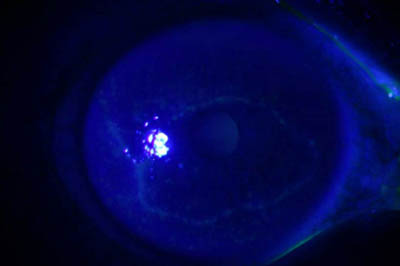

Anillo inmunológico de Wessely

- Es la expresión de la interacción de los antígenos extraños con los anticuerpos que se difunden desde los vasos limbares hacia el estroma.

- Representa la formación de un complejo inmune que activa el sistema del complemento.

- El anillo de Wessely contiene principalmente neutrófilos

- Puede aparecer en procesos no infecciosos